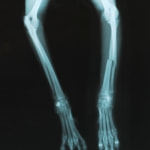

ペルシャ猫 11ヶ月齢 雄

他院にて左大腿骨遠位の成長板骨折(salter-harrisⅠ型)が認められており、治療相談を目的として来院。当院にて、キルシュナーワイヤーを用いたピンニングにより骨折部位の整復を行いました。術後の経過は良好で、現在も経過観察中です。

術後レントゲン

Arthrex社のターゲティングデバイスを用いてピンニングの位置を調整することで、確実な固定を行っています。当院ではこの手術器具以外にも、人の手術にも使用される様々な器具を導入し、手術精度を高め、また医療メーカーと新しい器具の開発、試作にも取り組んでおります。